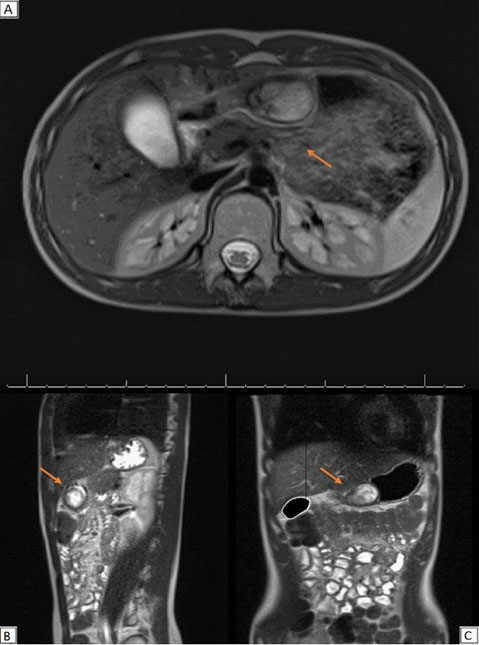

MRI scans of the abdomen confirmed a solid oval mass of 4 X 2,5 cm, with regular profiles (Figure 2). The mass arose from the pyloric antrum with upstream stomach dilated by fluid. It showed an hyperintense signal in T2-weighted sequences with no diffusion restriction to the ADC map and homogenous post-contrast enhancement. Imaging was suggestive of mesenchymal tumour.

Figure 2:Magnetic resonance imaging findings of the abdomen – MRI showing a mass developing inside the wall of the antrum with well-defined profiles. The lumen of the stomach is partially obliterated by the lesion. (A): Axial scan; (B): Sagittal scan; (C): Coronal scan.